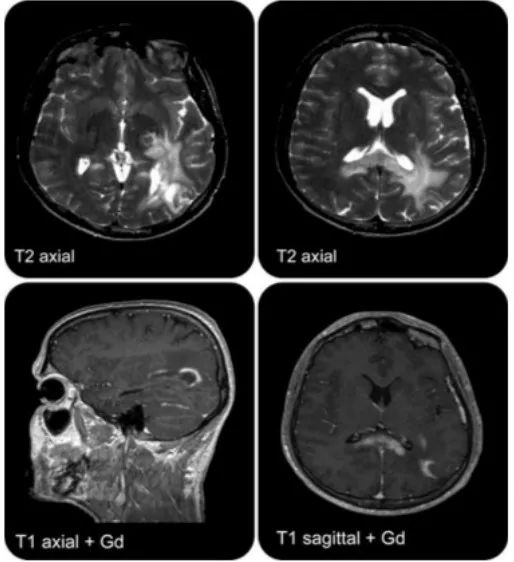

病例1(病例提供: 杜琴 老师)

患者,青年女性。患者入院前3小时于院外行“左侧颞部自体脂肪填充术”。2小时候后自觉头晕,随即出现失语。急诊取栓后两天去世。

答案:急性脂肪栓塞

本病例难度不高,目的是再次让老师们了解美容手术可能造成的致命性危害。自体脂肪注射是一种常见的面部软组织美容手术。虽然这种手术通常是安全的,但有个别患者在注射后出现视力丧失或脑梗死。患者大脑中动脉低密度灶,符合脂肪栓塞。颞部自体脂肪注入术时,注射针刺入颞浅动脉,高压注射下,脂肪碎块经颞浅动脉逆行入颈外动脉,经颈总动脉和颈内动脉再进入颅内导致颈内动脉供血系统的脑栓塞,和/眼供血受阻导致失明。因此,脂肪注射应缓慢进行,并确保注射器回抽没有血液。